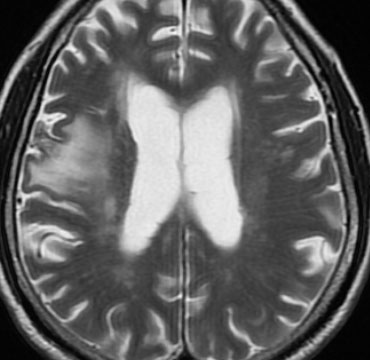

定位放射線治療後

治療は奏功して,腫瘍は縮小して周囲の脳浮腫(右側)も軽減しています。